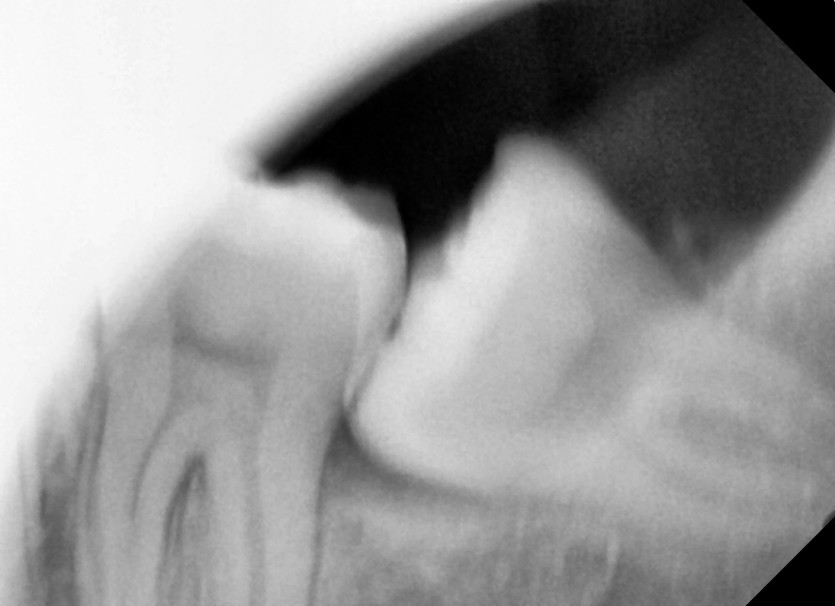

#38 사랑니 발치

구강 외과 전문의가 당일 발치했습니다.